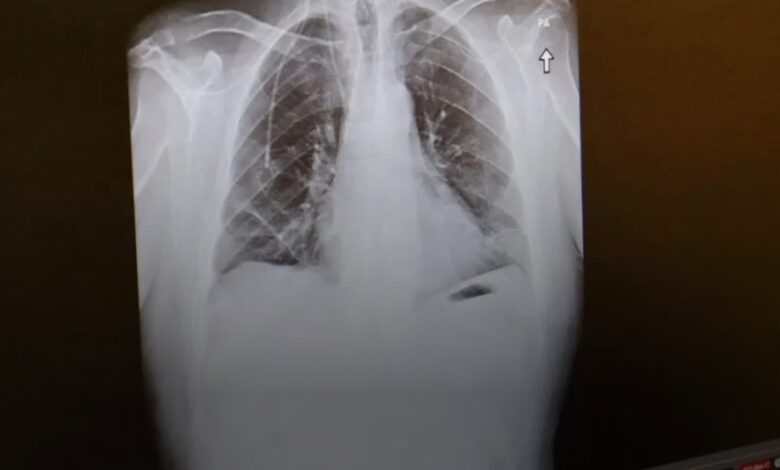

ما سرّ انتشار سرطان الرئة لدى غير المدخنين؟

ارتبطت الإصابة بسرطان الرئة منذ عقود بالتدخين، لكن زيادة نسبة الإصابة بهذا المرض لدى غير المدخنين دفع عدد من العلماء لتصنيفه كمرض مستقل يختلف عن فئات السرطان المعروفة سابقا، وله خصائص تميزه.